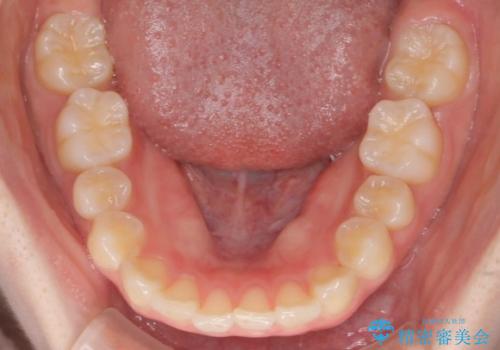

- 出っ歯を主訴に来院されました。今回は4番の歯を4本抜歯をし、ワイヤー矯正にて治療しました。

抜歯矯正のため2年を予定してましたが、予定よりも早く終わることができました。また口元も下がり、かみ合わせも改善しました。